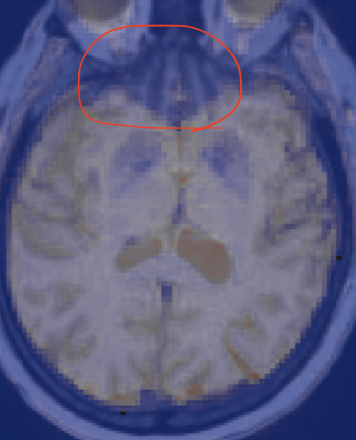

Another question I have is regarding the orbitofrontal area. You can see that the orbitofrontal area in the screenshot is not red as the rest of the brain, and the raw fMRI is that way, so it's not an alignment problem. It's as if that area is almost not getting any BOLD signals. I wanted to see if other people have experienced this and have any wisdom regarding why this might be happening.